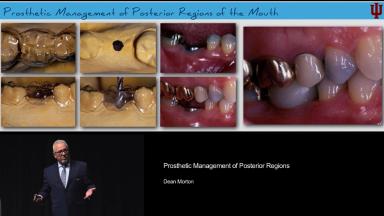

Prosthetic Management of Posterior Regions

This presentation highlights the critical considerations to treat posterior edentulous spaces with implant restorations from one of the most experienced clinicians in the field, Dr. Morton. With a series of clinical cases, he explains various factors influencing the treatment planning with posterior implant prostheses including implant and prosthetic designs, abutment and prosthetic materials, abutment connections, inter-arch space considerations, and nature of opposing dentition. The presentation highlights the management of clinical situations with adequate, inadequate, and excessive interocclusal spaces as well as available bone volume with careful selection of implant and prosthetic designs. The importance of digital implant planning and digital prosthetic designs for posterior restorations is emphasized.

- explain different implant treatment strategies in managing posterior edentulous spaces

- discuss prosthetic designs and material considerations for posterior implant restorations

- recognize clinical situations regarding available vertical restorative space to select appropriate implant and abutment design for long term success